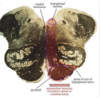

ID the structures

A

22

Q

ID the vessels